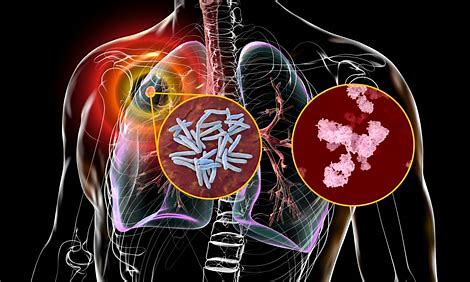

ക്ഷയരോഗം, പ്രധാനമായും ശ്വാസകോശത്തെ ബാധിക്കുന്ന ഒരു ബാക്ടീരിയൽ ഇൻഫെക്ഷൻ ആണ്. എന്നാൽ ഇത് ശരീരത്തിന്റെ മറ്റ് ഭാഗങ്ങളെയും ബാധിക്കാം. ഇത് ഒരു വ്യക്തിയിൽ നിന്ന് മറ്റൊരാളിലേക്ക് വായു മാർഗ്ഗം പകരാവുന്ന രോഗമാണ്.